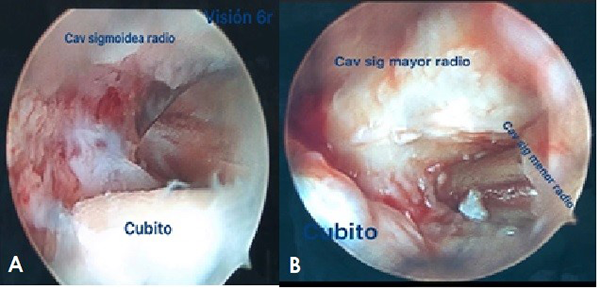

Efectuamos la artroscopía de las articulaciones radiocarpiana, cubitocarpiana y de la articulación radiocubital distal. Si nos encontramos con la parte central del CFCT intacta, realizamos una ventana circunferencial para poder trabajar y mirar hacia la ARCD. Se evalúa así la cabeza del cúbito y la superficie de la cavidad sigmoidea menor del radio observando la lesión cartilaginosa. Este procedimiento de diagnóstico artroscópico lo hacemos con visión 6R y palpador en portal RCDd.

Luego, realizamos un intercambio de portales, visión por 6R y trabajo por portal RCDd, donde efectuamos el fresado de la cavidad sigmoidea menor del radio y de la cabeza del cúbito. Ejecutamos el fresado completo de las superficies articulares hasta observar el hueso esponjoso completo en una visión de 360° por el portal RCDd.

Figura 4: Se observa por visión 6R y palpador por visión RCDd la artrosis de la ARCD.

Figura 5: Se observa por portales de trabajo 6R y RCDd el fresado de la cavidad sigmoidea menor del radio y la cabeza el cúbito en su porción articular con el radio.

Figura 6: Se observa el fresado final de la ARCD y la compresión de la articulación luego de la colocación del tornillo de artrodesis.